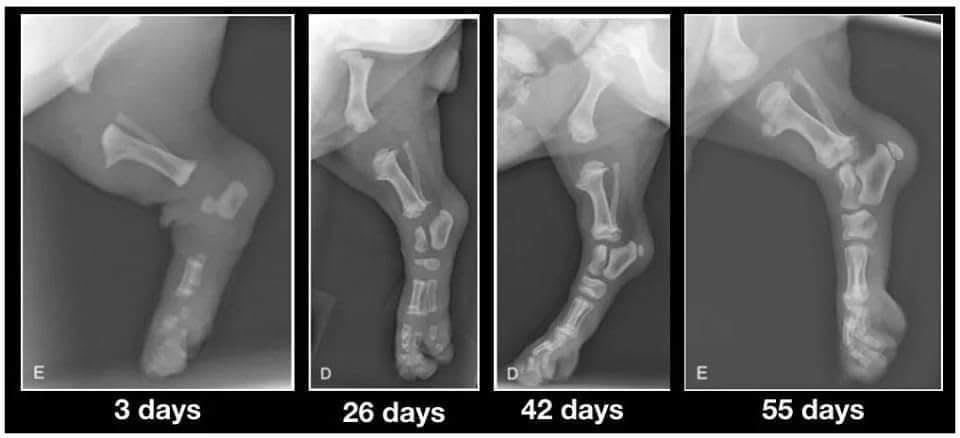

Lorsque vous accueillez enfin vos chiots de 9 semaines, veuillez garder cette image à l'esprit. Leurs os ne se touchent même pas encore. Ils marchent si joliment avec de grosses pattes souples et des mouvements bancals parce que leurs articulations sont entièrement constituées de cartilages, de muscles, de tendons et de ligaments recouverts de peau. Rien n'est encore bien ajusté ou n'a encore de véritable prise.

Lorsque vous les faites courir de manière excessive ou que vous ne limitez pas leur exercice pour les empêcher d'en faire trop pendant cette période, vous ne leur donnez pas la chance de grandir correctement. Chaque grand saut ou course bondissante et excitée provoque des impacts entre les os. En quantités raisonnables, ce n'est pas problématique et c'est une usure normale qui s’opèrera.

Mais lorsque vous laissez le chiot sauter du canapé ou du lit, l’emmenez faire de longues promenades, vous endommagez cette articulation en formation. Lorsque vous laissez le chiot se déplacer sur des carreaux glissants, vous endommagez l'articulation.

Vous n'avez la chance de les faire grandir qu'une seule fois. Un corps bien construit est quelque chose qui vient d'un excellent élevage et d'une bonne éducation. LES DEUX, pas seulement un.

Une fois adulte, vous aurez le reste de votre vie à passer à jouer et à vous engager dans des exercices à fort impact. Alors gardez-le au calme tant qu’il est encore petit et offrez-lui le cadeau qui ne peut être offert qu'une seule fois.